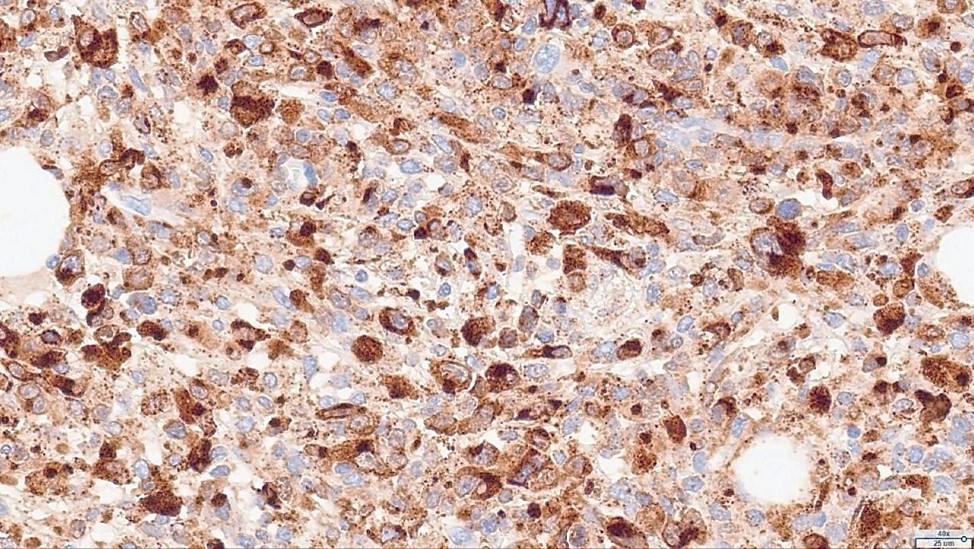

Histopathological examination revealed a non-circumscribed proliferation of large cells with marked nuclear pleomorphism, prominent nucleoli, and abundant clear cytoplasm, with numerous mitotic figures (Figure 3). Immunohistochemistry showed strong and diffuse expression of CD30 in atypical cells (Figure 4), and positivity for granzyme B, CD2, CD4, and CD25 in atypical T-cells (Figure 5). Numerous intermingled histiocytes were positive for CD68 and CD163, but negative in the atypical cells (Figures 6 and 7). ALK1 was negative in lymphoid cells (Figure 8). These findings supported the diagnosis of primary cutaneous anaplastic large cell lymphoma. Laboratory and PET-CT evaluation showed no extracutaneous disease. Localized electron beam radiotherapy was performed.

Figure 5: Immunohistochemistry: Granzyme B, CD2, CD4, and CD25—positive T-cell markers in atypical cells.